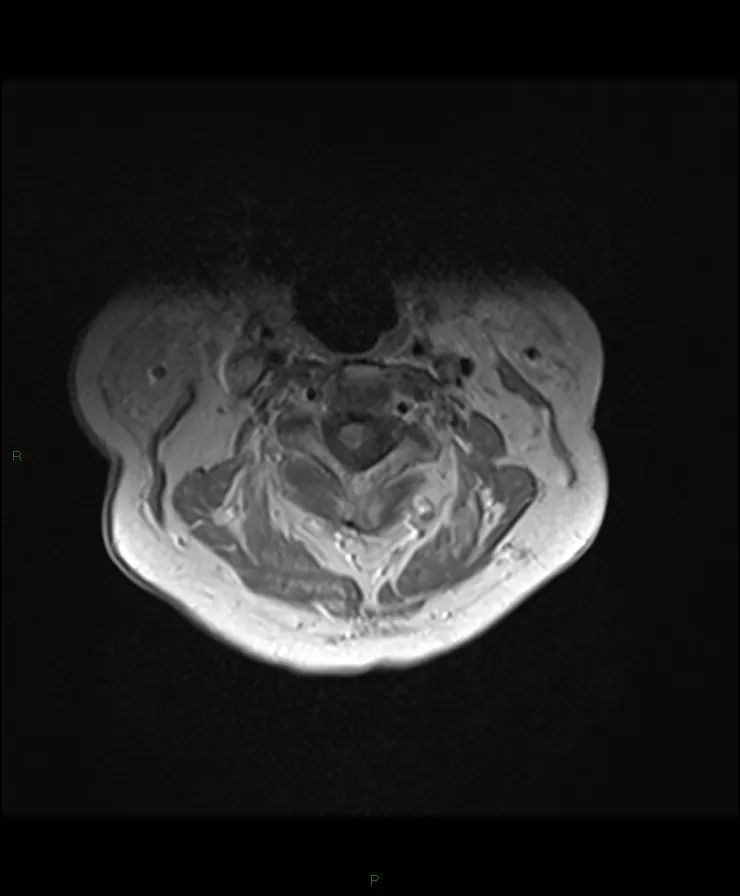

CASE M70 右肩进行性无力三个月。没有痛苦。

颈脊髓在C2和T1之间肿块,T1等信号,T2高信号,不规则的非均匀强化。